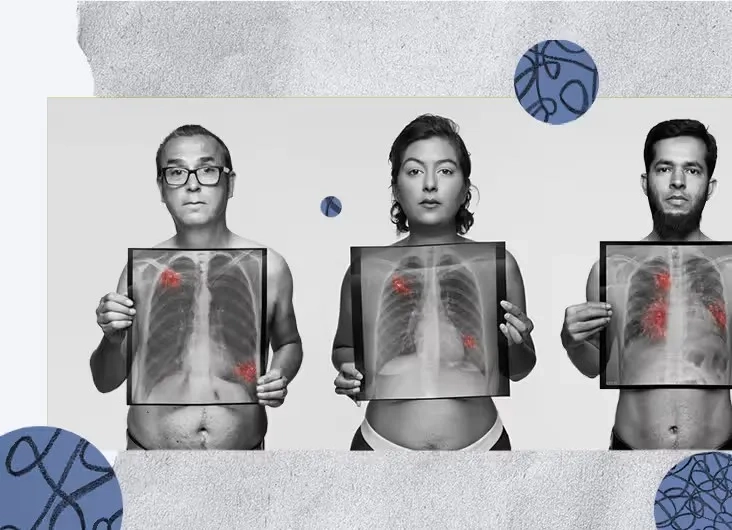

Image of the disease Lung Cancer - and other variables

Early detection through screening is critical for improving the lung cancer survival rate. If you have risk factors or symptoms, consult your doctor about diagnosis and treatment.